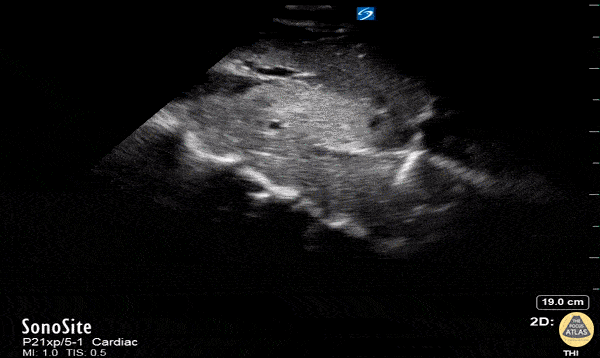

A 30-year-old man presented with shortness of breath. Normally fit and well with no past medical history apart from a lump in right axilla. Observations were stable apart from a high respiratory rate. Physical examination revealed more lymph nodes in the groin. Working diagnosis of Lymphoma and sent for a CT chest, abdomen and pelvis. In the interim, point of care ultrasound showed clot in the IVC. Confirmed on CT scan. Patient was ultimately diagnosed with metastatic testicular cancer and tumour thrombus in the IVC, which was managed conservatively with anticoagulation. Dr Parmy Deol, Emergency Physician, Chelsea and Westminster hospital, London